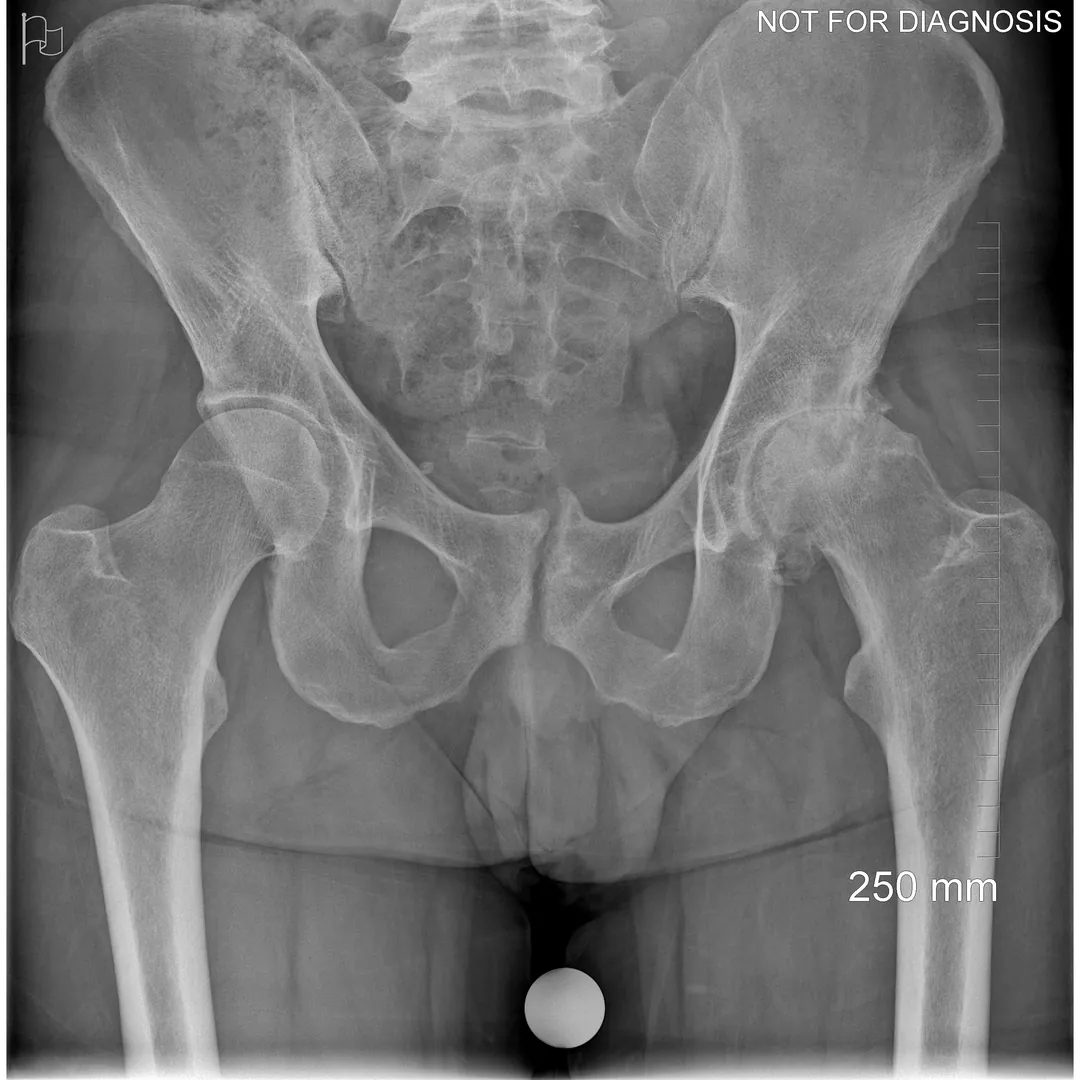

Hip resurfacing is a type of hip surgery used to treat hip arthritis, most commonly in younger and more active patients. Unlike a total hip replacement, hip resurfacing preserves more of your natural thigh bone. Instead of removing the entire femoral head (ball at the top of the thigh bone), the damaged surface is trimmed and covered with a smooth metal cap. The hip’s socket on the pelvis is also fitted with a metal cup.

Dr Grammatopoulos will review your X-rays and other imaging carefully to determine whether hip resurfacing is an appropriate option for you.

- Am I a candidate for hip resurfacing based on my X-rays and bone quality?